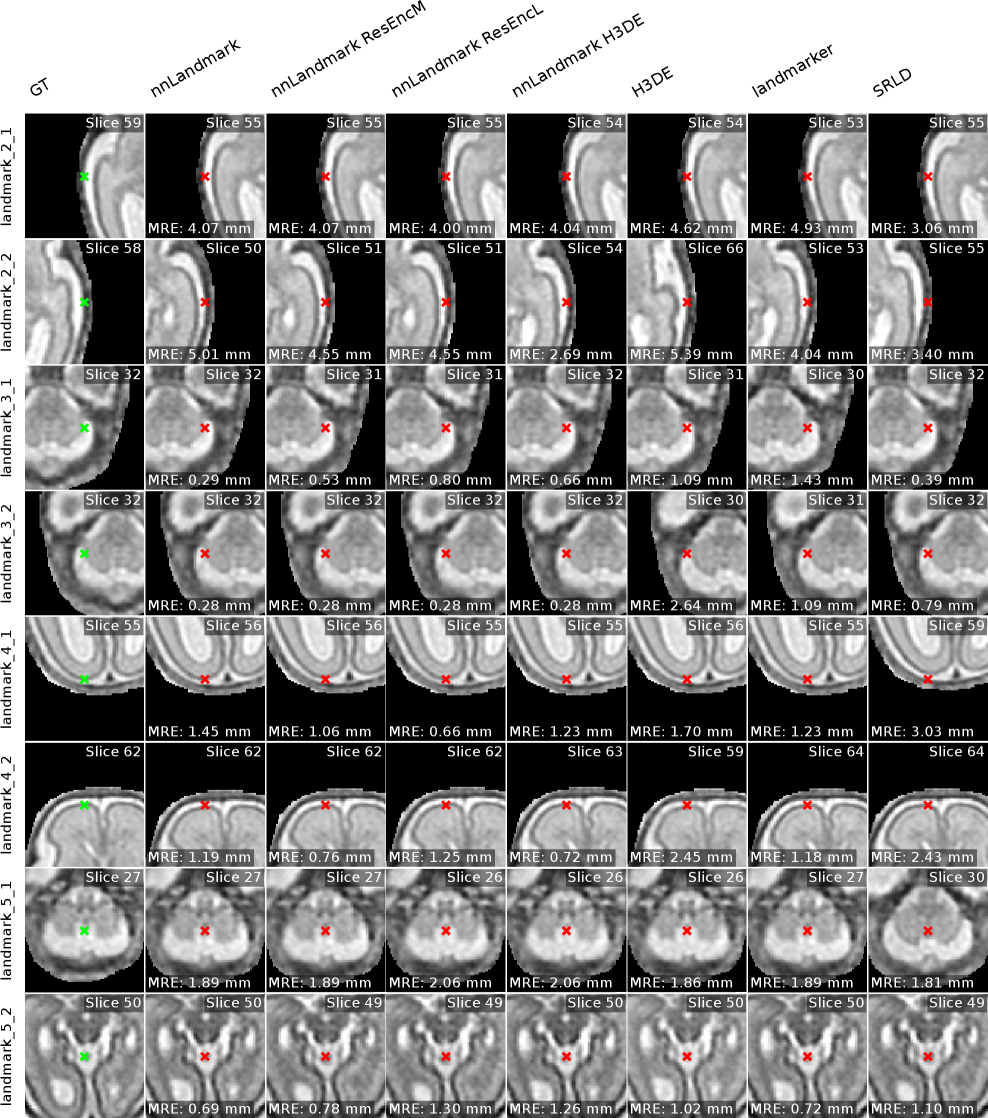

Randomly chosen example predictions for the nnLandmark ResEncM model for all datasets are shown in Figure 9. Visual examples for all methods are given in the Appendix F.